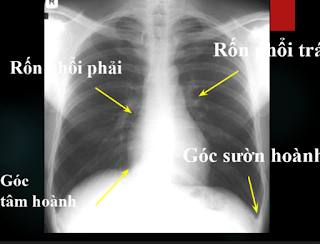

File hướng dẫn đọc X quang ngực gồm 49 trang, gồm các hình X quang ngực rõ nét, xinh động đặc biệt là có chú thích chi tiết.

Đánh giá phim x-quang đúng kĩ thuật:

Lồng ngực nằm trọn trên phim

Tư thế bệnh nhân

Thở vào đủ sâu: vòm hoành ở mức cung trước x.sườn 6 và cung sau x.sườn 10

Độ xuyên thấu của tia: thấy đs ngực 1,2,3 hoặc 4

Loại bỏ hết dị vật